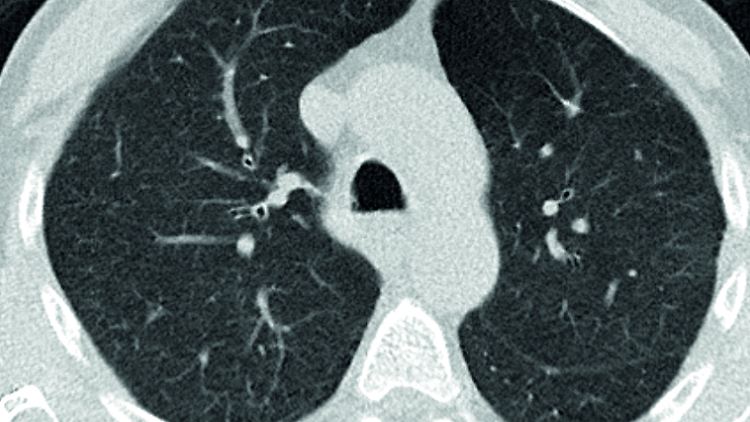

Computertomographie-Aufnahme (CT-Bild) der Lunge eines gesunden Menschen.

(Foto: picture alliance/dpa/Uniklinik RWTH Aachen/Institut für Pathologie)